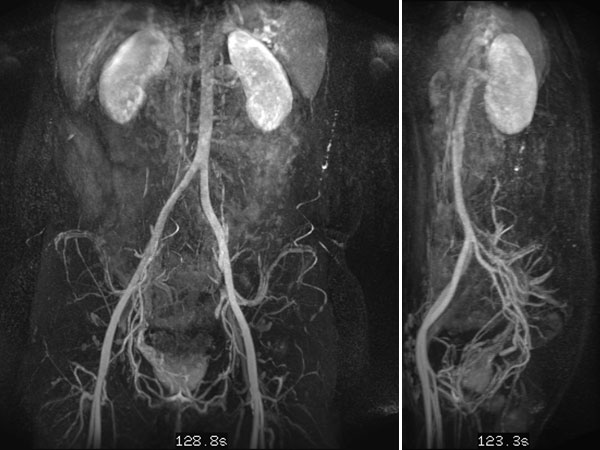

In der dynamischen, konstrastmittelunterstützten MR-Angiographie (hier Spätphase über 2 min nach i.v. Kontrastmittelgabe, links koronare und rechts sagittale Rekonstruktion) zeigt die Läsion keine Kontrastmittelanreicherung oder vermehrte Vaskularisation. Sie ist praktisch nicht sichtbar.